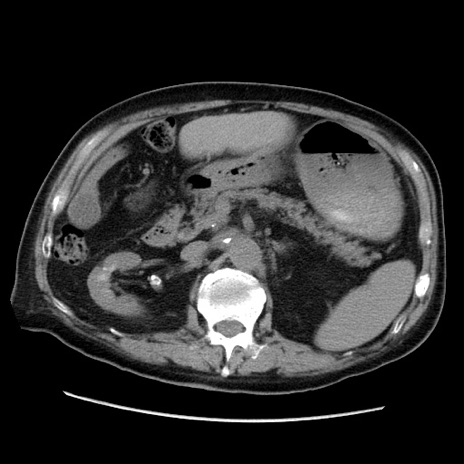

症例21(横断像)

【症例】70歳代男性

【主訴】腹痛

【現病歴】肝硬変・肝細胞癌にてかかりつけの方。約9時間前に食後より腹痛出現。症状が徐々に増悪し、嘔吐出現したため来院。

【既往歴】肝硬変、肝細胞癌(RFA、TACE後)

【身体所見】意識清明、表情苦悶様、BT 36℃、BP 129/78mmHg、P 88bpm、SpO2 97%(RA)、右上腹部から心窩部にかけて圧痛あり、反跳痛なし、筋性防御あり。

【データ】WBC 5800、CRP 0.16